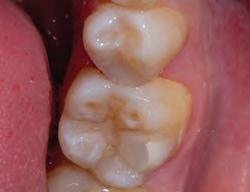

• Stains carious and demineralized dentin

• Provides precise, mess-free delivery

• Available in dark green for working near pulp

Sable Seek caries indicator contains FD&C dyes, and Seek caries indicator contains D&C dyes in a glycol base. Both are used to stain carious and demineralized dentin.

Seek and Sable Seek caries indicators stain carious and demineralized dentin and can be very useful for difficult-to-see areas, for example; undercuts of preparations, dark dentin, areas along the DE junction, etc. Green Sable Seek caries indicator helps visualization of decay in deep caries cases to help avoid pulp exposures.

PROCEDURE

dentin) with slow-speed round bur or excavator. To control overexcavating near the pulp, remove final portion of caries with hand excavator.